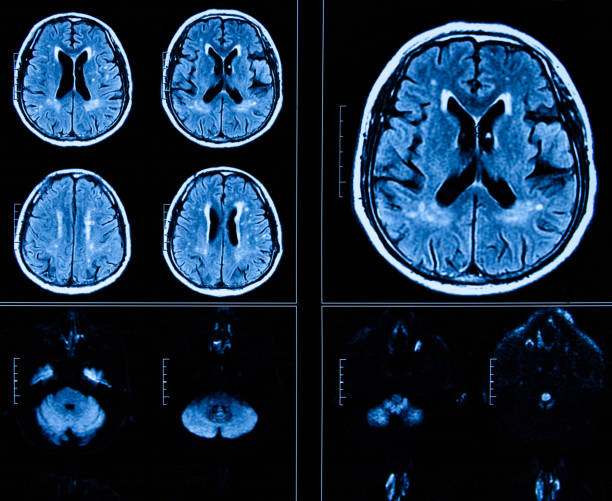

뇌 일부분에 혈액이 제대로 공급되지 않으면 혈관이 막히거나 터지기 때문에 뇌가 손상되며 여러 이상이 발생할 수 있는데 이러한 증상을 일컬어 뇌졸중이라고 합니다. 뇌졸중을 유발하는 원인에는 비만, 불규칙한 생활습관, 고혈압, 흡연 등으로 유발될 수 있으며 나타나는 전조증상들이 어쩌면 가볍게 넘길 수 있는 증상들이 많다보니 단순히 노화로 인한 증상으로 가볍게 여기는 경우도 있기 때문에 초기 대응이 어렵습니다. 따라서 이번 시간을 통하여 뇌졸중 전조증상에 대해 자세히 알아보고 초기 대응력을 높이시기 바랍니다.